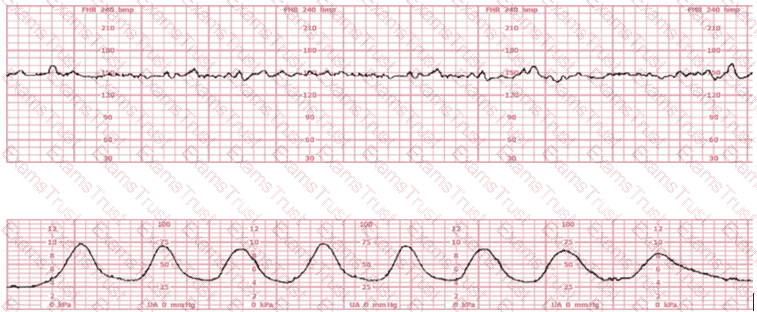

A woman (G1P0) arrives in triage with a pain score of 4/10 at 39-weeks gestation. The fetal heart rate tracing shown is obtained. The best intervention is to: